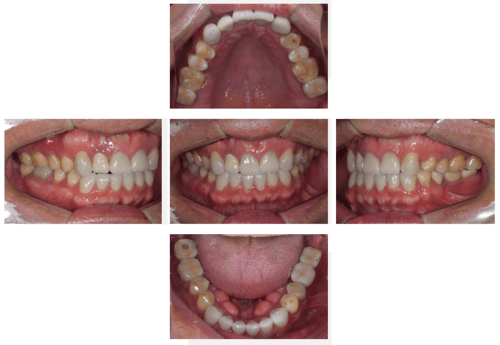

口腔内写真

- Befor

- After

| 年齢 | 50代・男性 |

|---|---|

| 主訴 | 左上7番 左下5番7番 |

| 治療内容 | ・インプラント埋入 ※1:GBR(骨造成)・・・骨再生誘導法。骨の高さや厚みを人工骨や人工膜などを使用し再生する方法 |

| 治療費 | 合計:1,809,500円(税込) ■内訳 ・左上7番 ・左下5番7番 |

| 治療期間 | 左上7番約1年 左下5番7番約10ヵ月 |

| 治療方針 | 左上7番は昔他院で被せものをしており、被せものの中が歯ぐきの中まで虫歯になっていたため抜歯せざるを得ない状態だった。抜歯と同時に骨造成を行い、骨が出来るまで4ヵ月待ってからインプラントを埋入した。 ※2ポンティック・・・歯のない部分を補うダミーの歯。 |

| 担当者所見 | 元々金属の被せものが多く入っていたため、2次カリエス※3が多かった。今回は金属ではなく、ジルコニアを使用し、2次カリエスにならないよう、患者様にはブラッシング指導とメンテナンスの重要性をお伝えした。 ※3二次カリエス・・・詰め物や被せものを入れた歯が虫歯になること。 |